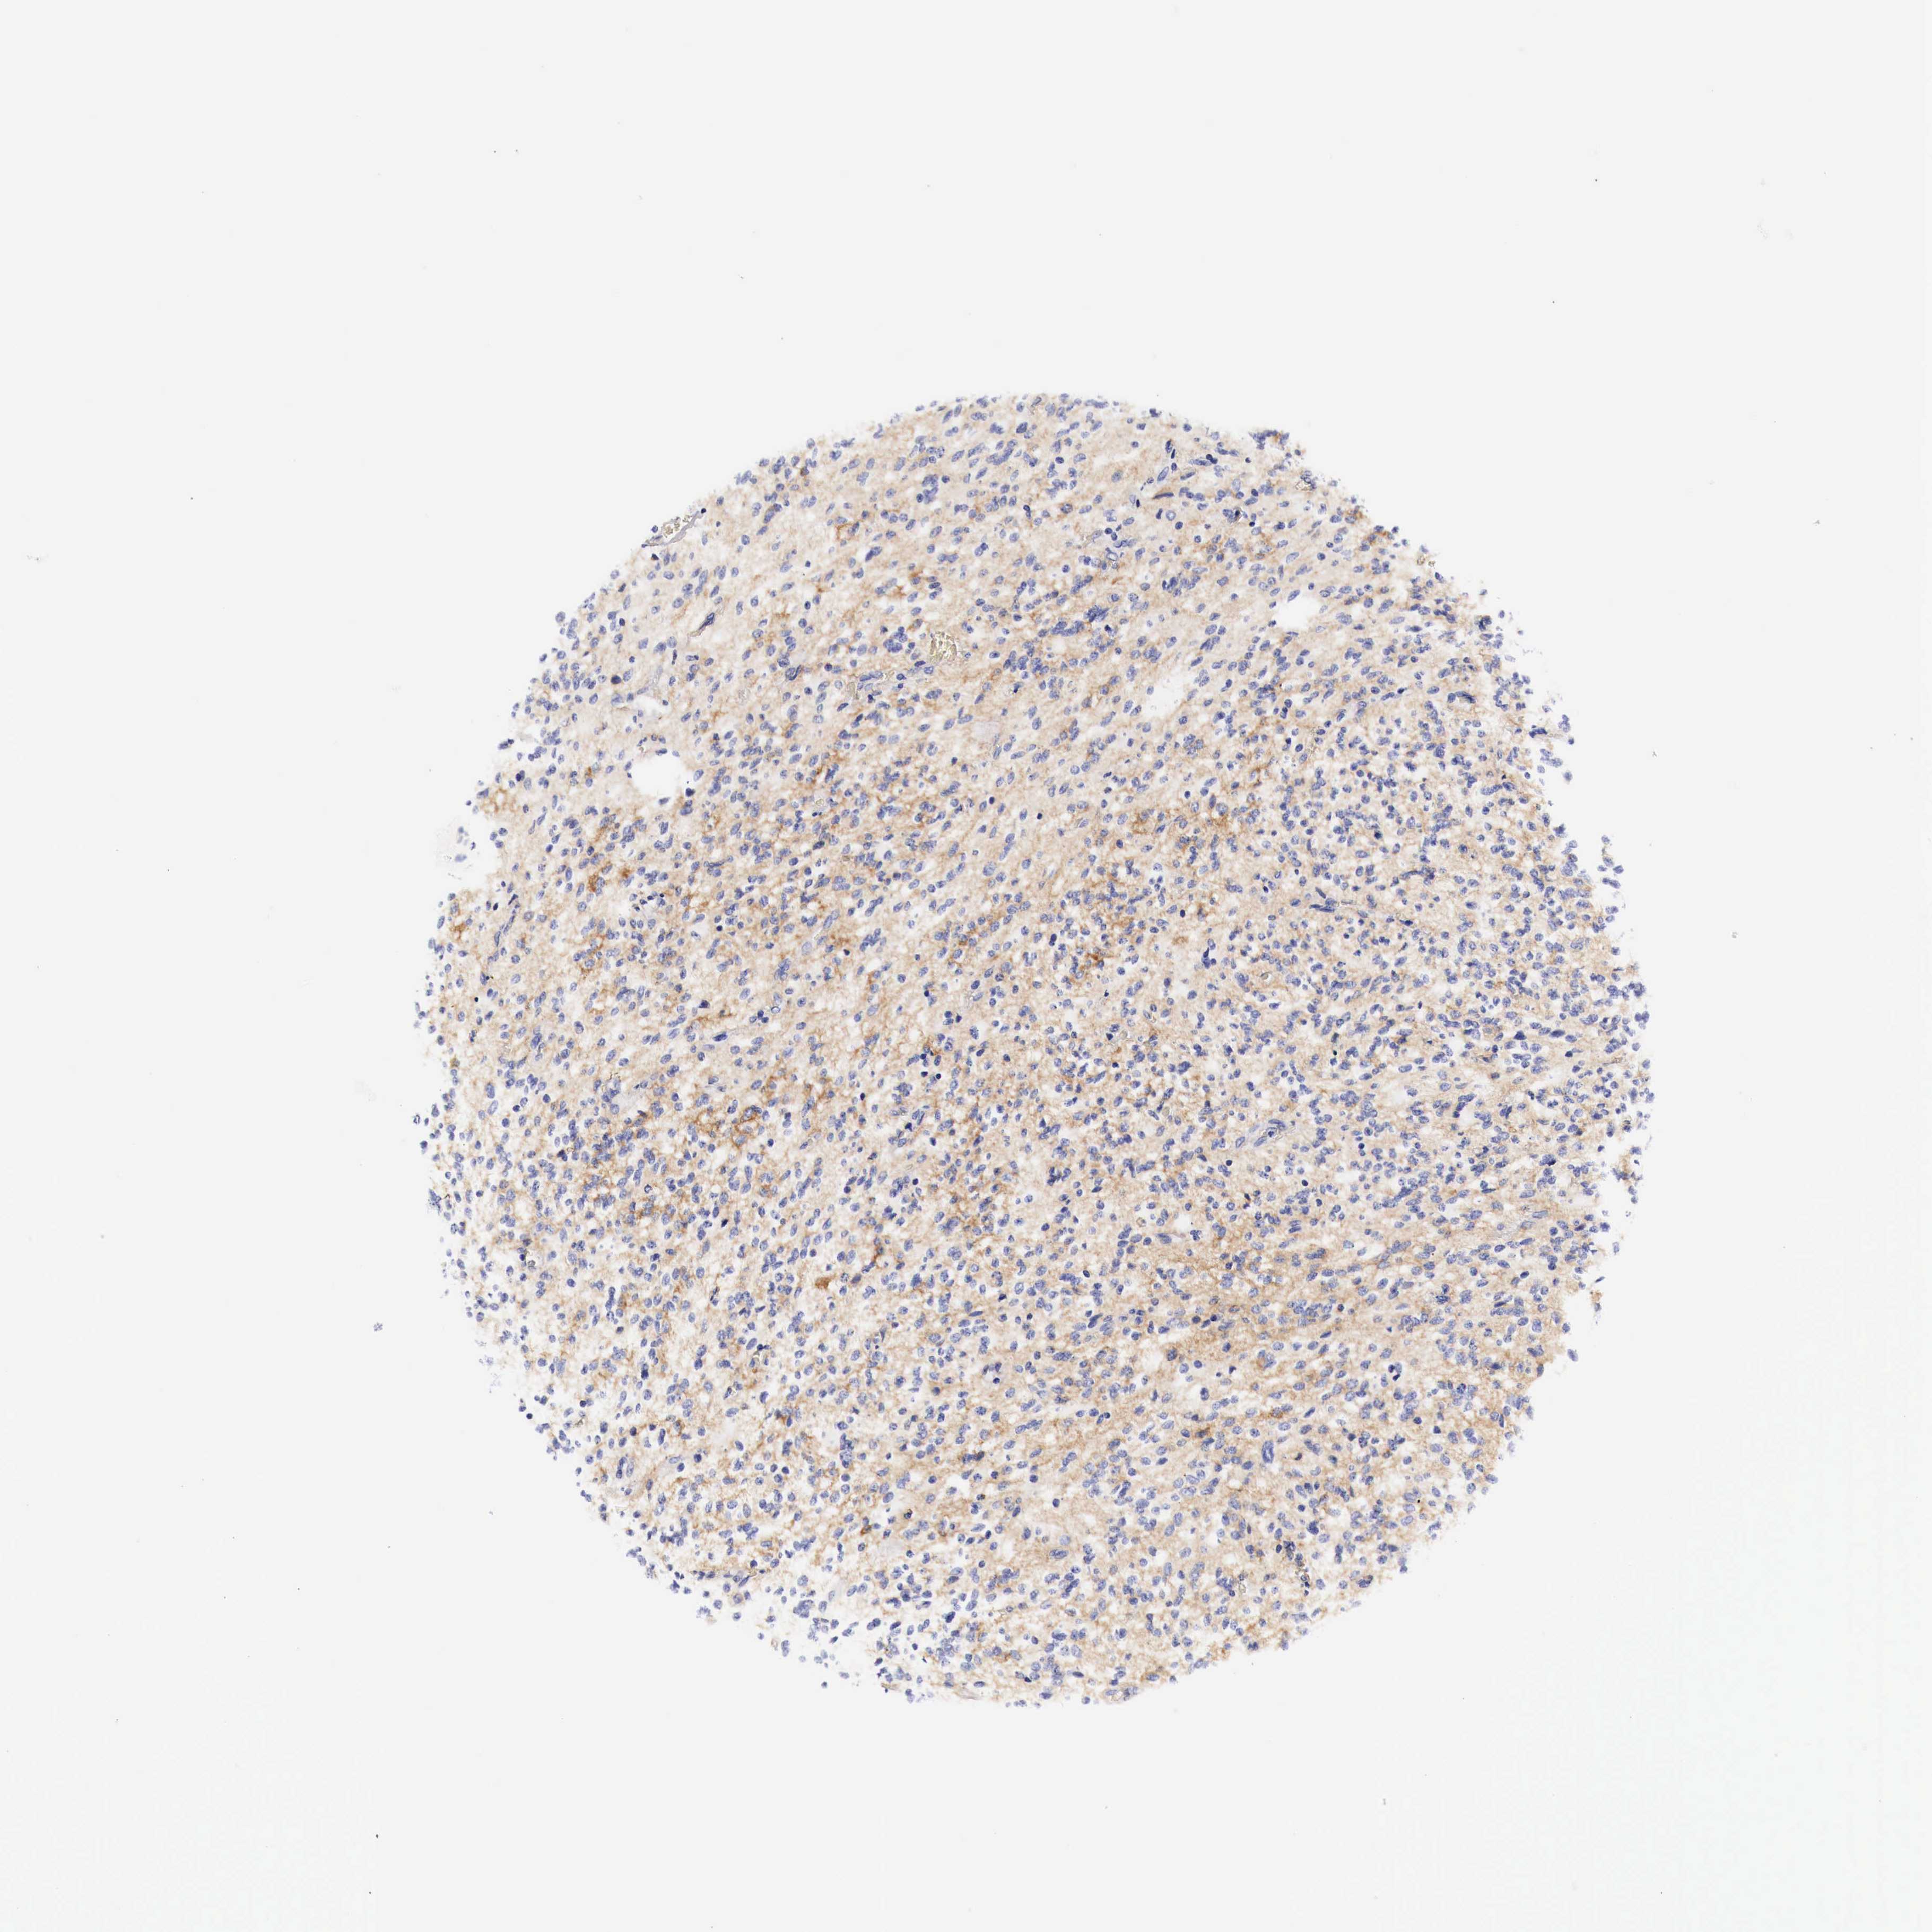

GLIOMA - Protein expressioni

A mouse-over function shows sample information and annotation data. Click on an image to view it in a full screen mode. Samples can be filtered based on level of antibody staining by selecting one or several of the following categories: high, medium, low and not detected. The assay and annotation is described here.

Note that samples used for immunohistochemistry by the Human Protein Atlas do not correspond to samples in the TCGA dataset.

Antibody stainingi

Antibody staining in the annotated cell types in the current human tissue is reported as not detected, low, medium, or high, based on conventional immunohistochemistry profiling in selected tissues. This score is based on the combination of the staining intensity and fraction of stained cells.

Each image is clickable and will lead to virtual microscopy that enables deeper exploration of all samples and also displays staining intensity scores, fraction scores and subcellular localization as well as patient and tissue information for each sample.

Glioma, malignant, High grade

Glioma, malignant, Low grade

Glioma, malignant, NOS